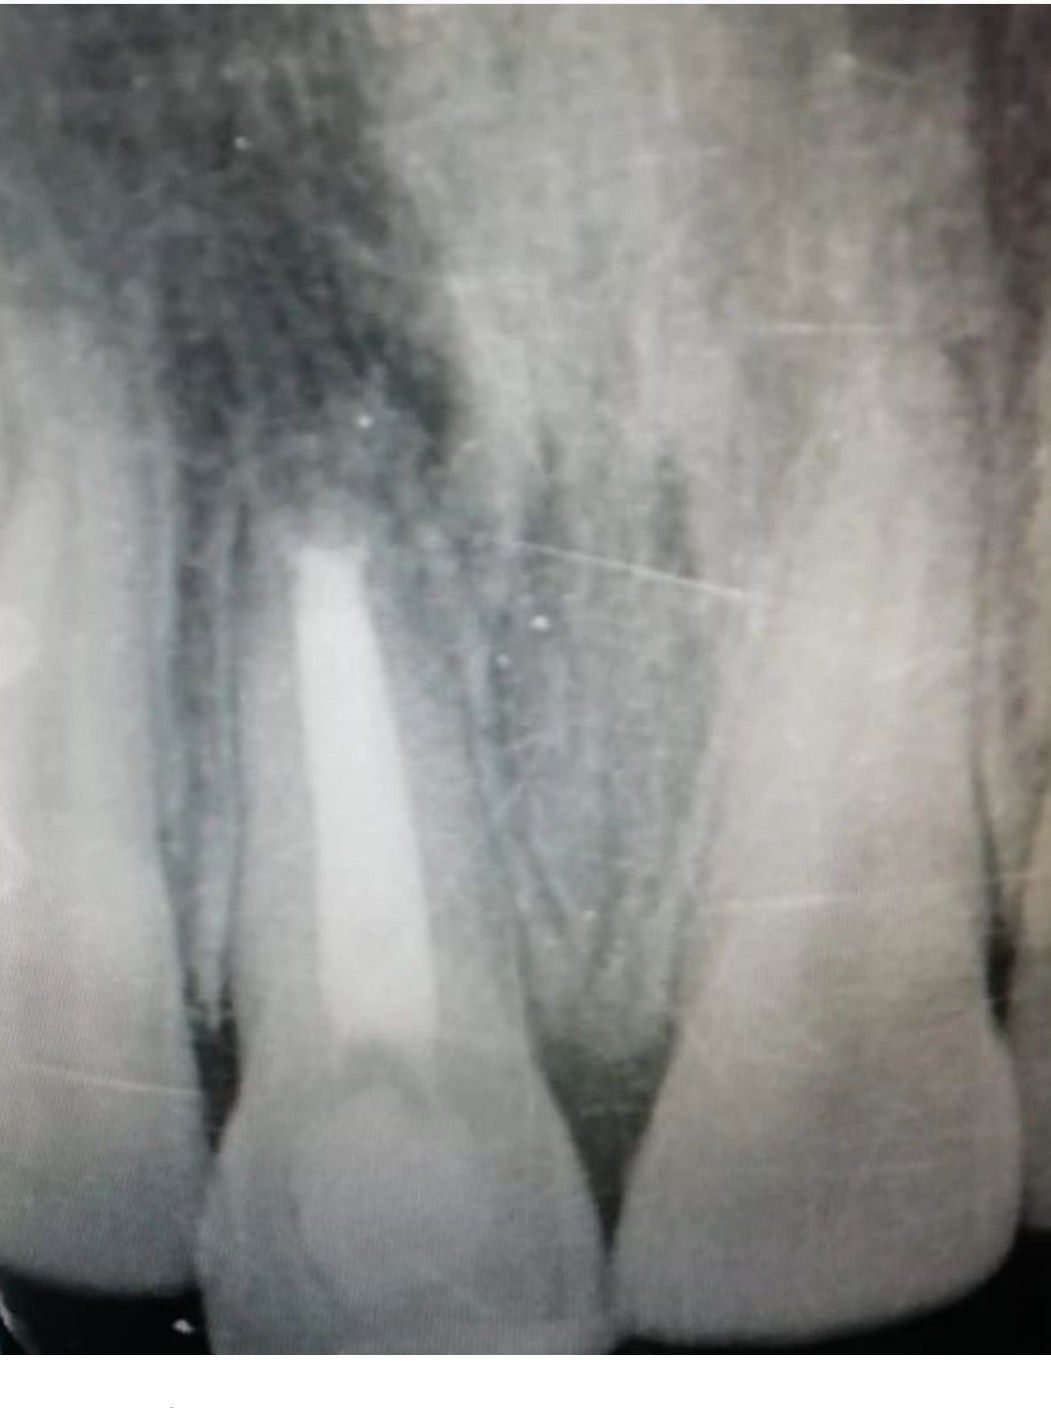

Apexification by Calcium hydroxide in necrotic immature central incisor. ⭐ The apical diameter ranges from 2-3.5 mm. ⭐ It takes 3-10 months for apical barrier to develop. ⭐ The type of apical barrier are 65% cap, 25% bridge and 10% ingrown wedge. ⭐ Rubber dam is applied, debridement done, canal is irrigate, then dried with paper points. ⭐ Root canal is then filled with Caoh by placing needle 2mm short of apex, then introducing Caoh slowly and withdrawing, take xray to evaluate any void, if there is any void specially in apical region, reintroduce the Caoh. ⭐ At recall, observe formation of apical barrier, if Caoh is partially absorbed, repeat the whole process, untill apical closure is achieved. ⭐ Seal the chamber with temporary Zinc-oxide eugenol cement. ⭐ If apical barrier is formed, measure the closure by radiograph and instruments. Lateral obturation is done, and permanent restoration given. ⭐ Keep patient on followup. By: https://www.instagram.com/p/CtZiUz7IYIO/?utm_source=ig_web_copy_link&igshid=MzRlODBiNWFlZA==